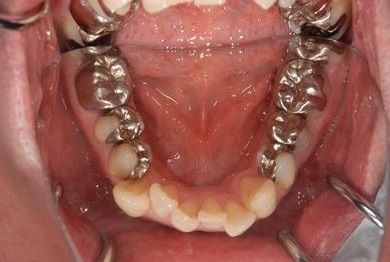

治療後

• 治療後